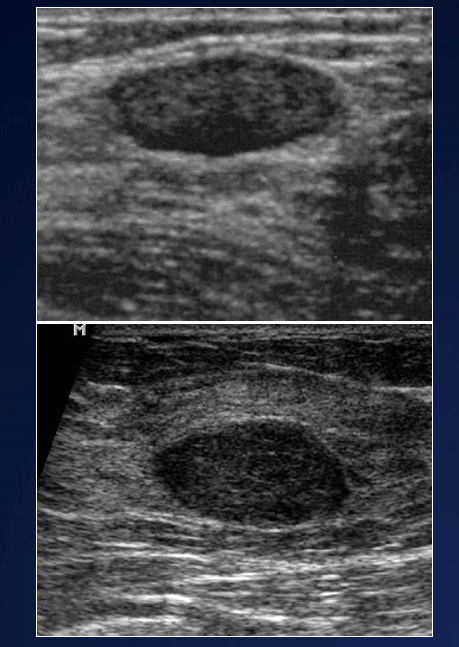

Describe the appearance of benign solid breast lesions on US

A

• Circumscribed - good borders

• Hypoechoic/hyperechoic

• “Wider than Tall”

• Homogeneous - lesions look similar

• Peripheral/no vascularity

• Often Multiple